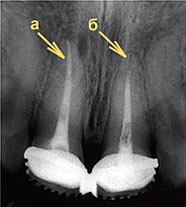

Пульпит — воспаление внутренних структур зуба (пульпы).

Лечение направлено на устранение воспалительного процесса и болевого синдрома. В начальных стадиях заболевания возможно излечение с сохранением тканей, питающих зуб. Для этого удаляют размягченный дентин и проводят медикаментозную обработку образовавшейся полости (антибактериальные препараты, препараты кальция и т.п.). Полость пломбируют, восстанавливая целостность и функцию зуба. При вовлечении в воспалительный процесс значительного количества пульпы зуба необходимо частичное или полное ее удаление. Развитие гнойного процесса требует вскрытия полости зуба, удаления гноя и проведения общей антибактериальной терапии.